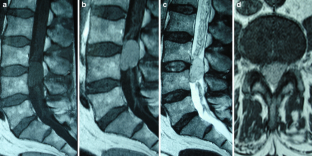

Fig. 3